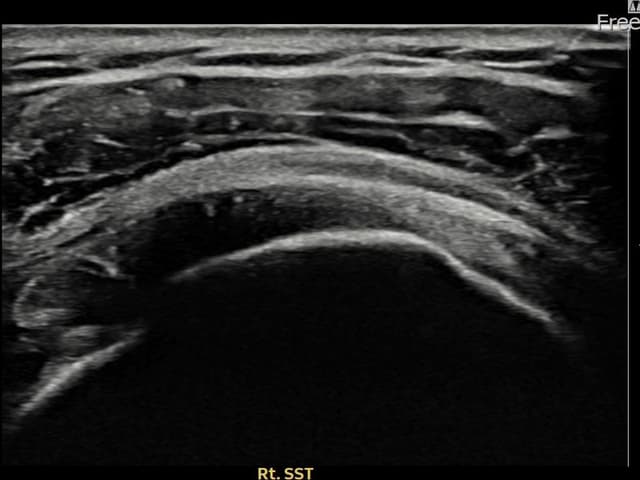

実際の患者様の施術前後の超音波画像。

手術なしで実現できる回復をご確認ください。

[経過期間: 23.09.01~23.11.03]

[縫縮術] 超音波検査にて右 棘上筋腱 滑液包面側部分断裂(8mm × 4mm (腱厚の約35%欠損))を確認。縫縮術施行後、腱の連続性が回復し、日常生活に復帰されました。